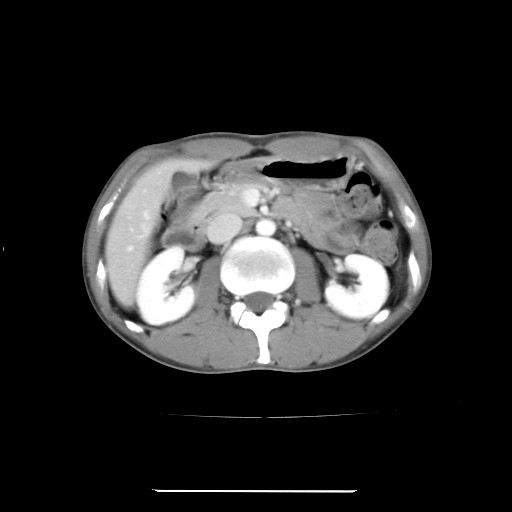

まずは先週。2011/12/12.